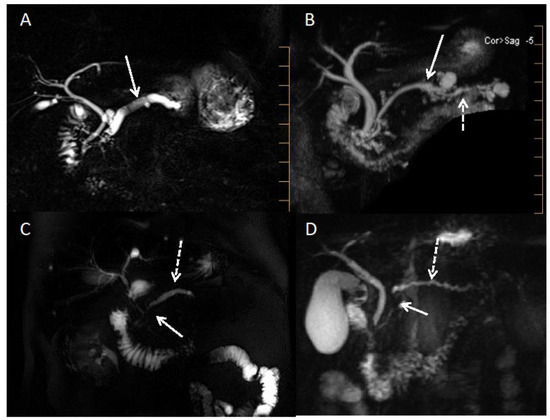

- Boninsegna, E.; Manfredi, R.; Negrelli, R.; Avesani, G.; Mehrabi, S.; Pozzi Mucelli, R. Pancreatic Duct Stenosis: Differential Diagnosis between Malignant and Benign Conditions at Secretin-Enhanced MRCP. Clin. Imaging 2017, 41, 137–143. [Google Scholar] [CrossRef]

- Wolske, K.M.; Ponnatapura, J.; Kolokythas, O.; Burke, L.M.B.; Tappouni, R.; Lalwani, N. Chronic Pancreatitis or Pancreatic Tumor? A Problem-Solving Approach. RadioGraphics 2019, 39, 1965–1982. [Google Scholar] [CrossRef]

- Schima, W.; Böhm, G.; Rösch, C.S.; Klaus, A.; Függer, R.; Kopf, H. Mass-Forming Pancreatitis versus Pancreatic Ductal Adenocarcinoma: CT and MR Imaging for Differentiation. Cancer Imaging 2020, 20, 52. [Google Scholar] [CrossRef]

- Elsherif, S.B.; Virarkar, M.; Javadi, S.; Ibarra-Rovira, J.J.; Tamm, E.P.; Bhosale, P.R. Pancreatitis and PDAC: Association and Differentiation. Abdom. Radiol. 2020, 45, 1324–1337. [Google Scholar] [CrossRef]

- Srisajjakul, S.; Prapaisilp, P.; Bangchokdee, S. CT and MR Features That Can Help to Differentiate between Focal Chronic Pancreatitis and Pancreatic Cancer. Radiol. Med. 2020, 125, 356–364. [Google Scholar] [CrossRef]